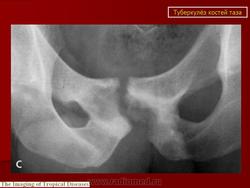

При рентгенологическом исследовании в преартритической фазе самым ранним симптомом является остеопороз, который может быть незначительным и выявляться лишь на сравнительных рентгенограммах с захватом двух тазобедренных суставов. Еще до появления туберкулезного остита могут отмечаться изменения со стороны мягких тканей в виде увеличения теней межмышечных прослоек между контурами суставной сумки и малой и средней ягодичными мышцами (симптом Ланге - Будинова). Отмечается также асимметрия костей малого таза (симптом Пинхасика), обусловленная неправильным положением больного из-за атрофии мышц, или наоборот утолщением сустава на больной стороне, или вследствие болевой контрактуры. Зная наиболее частую локализацию туберкулезных оститов вокруг тазобедренного сустава можно выявить участки нарушения костной структуры, нечеткость костных трабекул. Спустя 1,5-2 месяца выявляются очаги деструкции костной ткани с нечеткими неровными контурами, которые могут содержать множественные губчатые секвестры. Наиболее часто туберкулезные оститы располагаются в костях, образующих вертлужную впадину, реже они встречаются в шейке, и как исключение в головке бедренной кости. Причем очаги деструкции костной ткани, расположенные в вертлужной впадине, лучше выявляются на задних рентгенограммах, а очаги деструкции в шейке бедра, особенно в нижне-внутреннем отделе ее лучше выявляется на рентгенограммах с отведением бедра (по Лауенштейну). У некоторых больных наблюдается ранняя деформация ядра окостенения головки бедра в виде его увеличения.

Артритическая фаза (при переходе процесса на сустав) на рентгенограммах характеризуется усилением остеопороза, который постепенно распространяется на все кости нижней конечности. Суставная щель асимметрично суживается, больше в верхне-наружных отделах. В дальнейшем сужение суставной щели достигает значительной степени. Суставные поверхности костей теряют свои очертания, их контуры становятся нечеткими, неровными. Выявляются краевые, без четких контуров содержащие секвестры, очаги деструкции костной ткани. Последние могут вызывать значительные разрушения вертлужной впадины, головки и даже шейки бедренной кости, смещение головки бедра вверх.